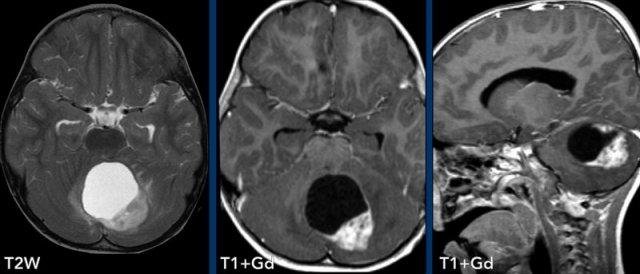

Các hình ảnh này của một trẻ 3 tuổi cũng nhập viện vì đau đầu.

Có hai dấu hiệu quan trọng cần lưu ý.

Hãy quan sát kỹ các hình ảnh trước khi tiếp tục đọc.

Hình ảnh

Nang lớn có nốt ngấm thuốc ở hố sau.

Lưu ý thành nang có ngấm thuốc.

Nốt không nằm ở phía màng mềm (phần trong của màng não) khác với trường hợp u nguyên bào mạch máu.

Kết luận

Chẩn đoán có khả năng nhất ở độ tuổi này là u nguyên bào thần kinh đệm lông.

Thành nang ngấm thuốc là một phần của khối u và cần được phẫu thuật cắt bỏ.